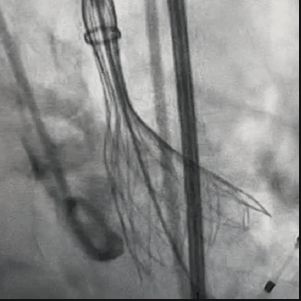

从三叶瓣重度钙化到二叶瓣畸形的根部解剖,从单纯主动脉瓣反流到入路极端迂曲挑战的案例。TaurusOne凭借其优异的柔顺性,支撑力强及内外层双侧裙边的特点,都能从容应对复杂的临床患者解剖结构。从患者的临床选择到术后的长久获益,从手术入路的种类到术中操作的注意事项,从围术期卒中的循证医学到术后的抗凝抗栓用药规范,在线专家共同交流彼此中心的围术期TAVR经验和分享现阶段经导管主动脉瓣置换的诊疗策略。针对当前TAVR领域多个热点学术问题进行了热烈的讨论,现场可谓精彩纷呈、高潮迭起。专家们纷纷借此契机相互交流探讨,分享各自的单中心经验,力求进一步提升TAVR手术的安全性和有效性,为主动脉瓣相关疾病的患者带来长远综合获益。